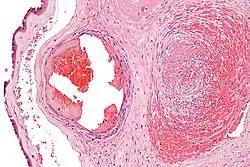

La fibrine ne préexiste pas dans le sang ; elle n'apparaît qu'au moment de la coagulation. La coagulation est la transformation du fibrinogène (soluble) par la thrombine en fibrine insoluble qui conduit à la formation d'un caillot. Dans un caillot, la fibrine forme un maillage qui emprisonne les cellules sanguines.